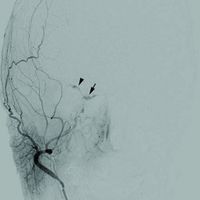

Selective angiography of the external carotid artery showing an indirect type D right carotid cavernous fistula, filling of the cavernous sinus (arrow) and retrograde drainage into the right superior ophthalmic vein (arrowhead) [1]

ويستند ذلك إلى التصوير بالرنين المغناطيسي، تصوير الأوعية بالرنين المغناطيسي والمسح الضوئي. تصوير الأوعية بالطرح الرقمي الدماغي (DSA) يعزز رؤية الناسور.